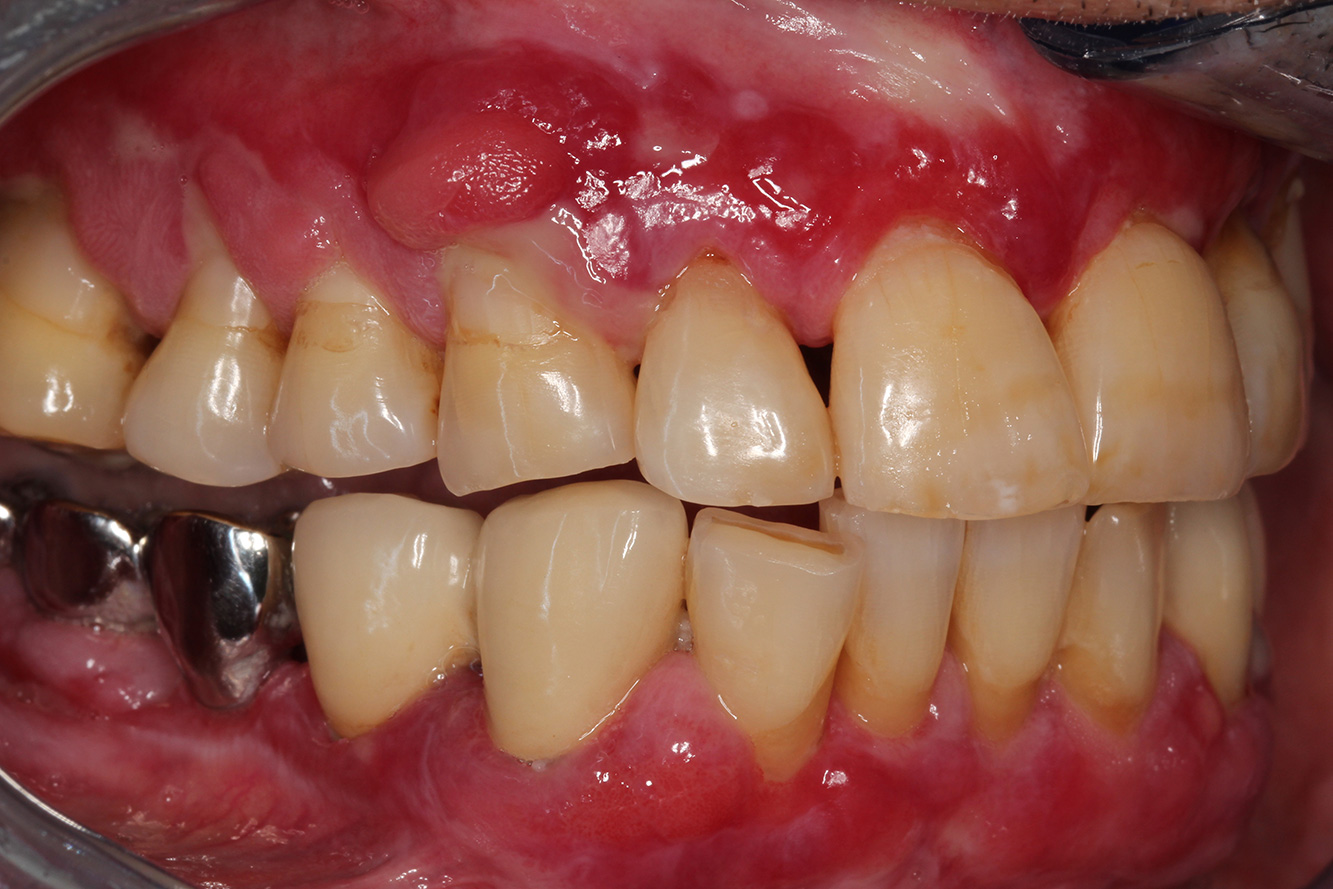

A 71-year old patient presents with having previously undergone a kidney transplant and with a history of hypertonia (high blood pressure). Due to his medical history, long-term medication with cyclosporine is required to suppress the immune system, as well as amlodipine to lower blood pressure. The patient also reports sensitive and bleeding gums. From an oral health perspective, the patient has undergone dental restoration and has eight missing teeth, pronounced gingival growth, and grade B, stage II periodontitis with active pockets and initial root caries on tooth 22. The caries risk assessment determines a moderate risk of caries (API 60). The following treatment recommendations can be determined for the prophylaxis session.

Based on the patient’s medical history, it is possible to identify a particular risk of complications. Due to the kidney transplant, the patient is immunosuppressed (cyclosporine), and therefore has a weakened immune system and requires infection prophylaxis (recommendation: 2 g of amoxicillin as an antibiotic, 1 hour before the session). At the same time, the patient’s long-term medication carries an increased risk of disease, as the gingival overgrowths identified are associated with this medication (20).

The patient’s situation must be addressed, especially when it comes to motivation and instruction. Due to the gingival overgrowths, the patient finds it difficult to practise good oral hygiene at home. The increased susceptibility to infection as well as the progression and emergence of the overgrowths (22) should be discussed at the patient’s level. At the same time, the patient should be instructed in hygiene techniques that are tailored to his individual needs.